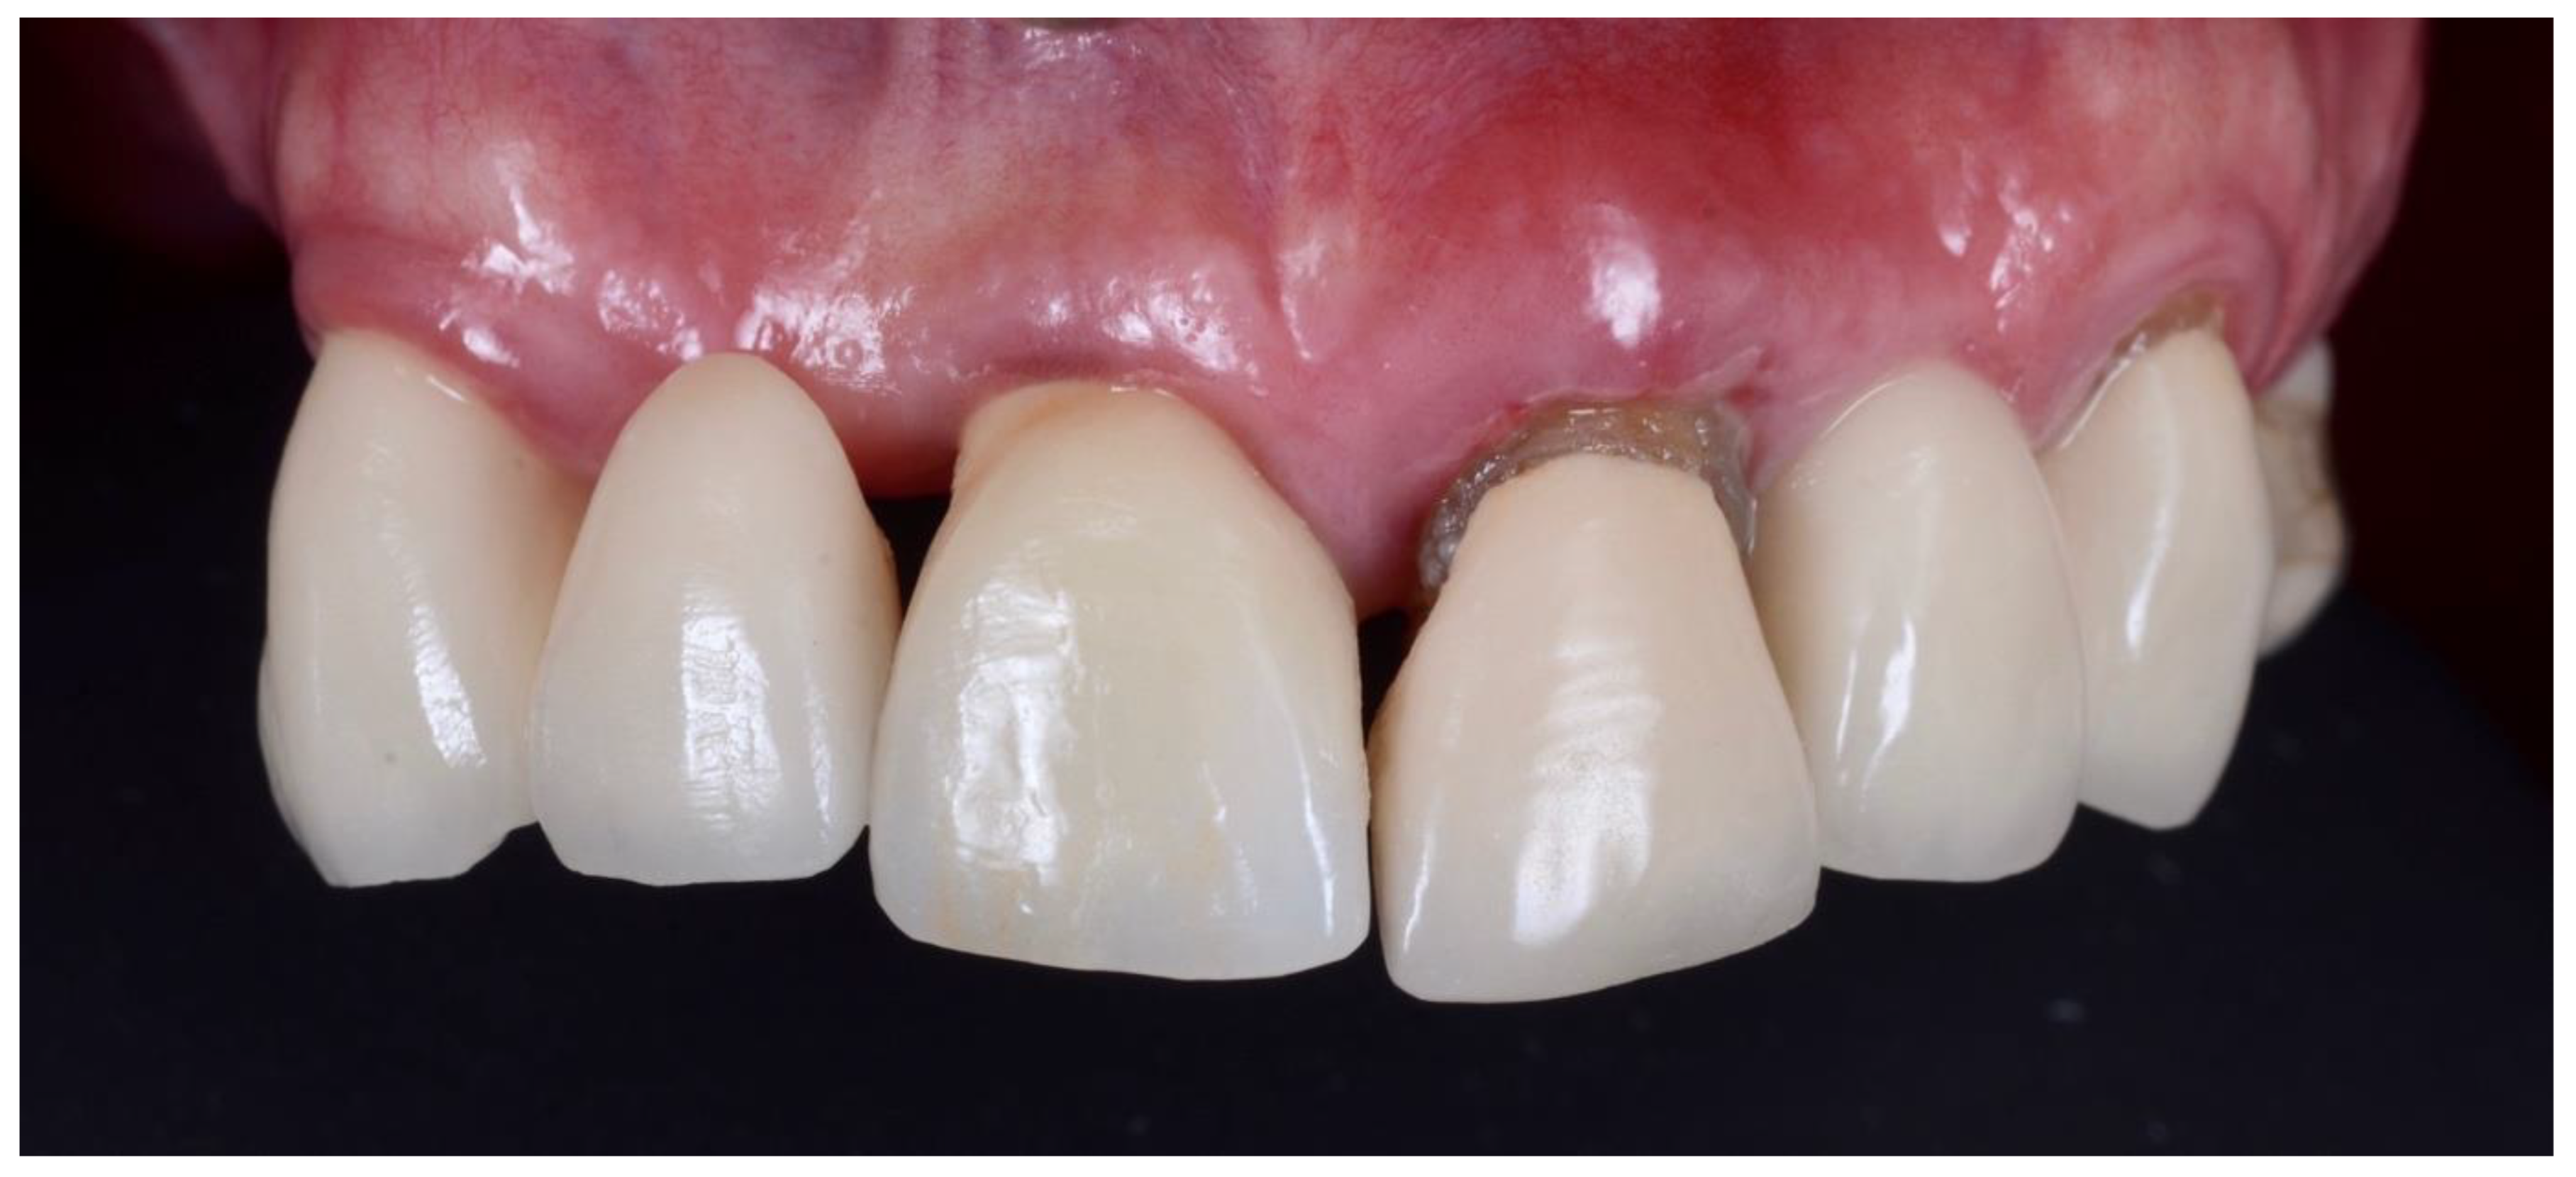

2.1. Surgical Technique